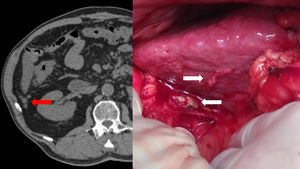

Varón de 68 años, portador de marcapasos y válvula aórtica mecánica, con antecedente de colecistectomía laparoscópica. figura 1

Se realiza tomografía computarizada por molestias abdominales, pérdida de peso y elevación del antígeno carcinoembrionario, observándose nódulos peritoneales en el flanco derecho sugestivos de carcinomatosis peritoneal.

Durante la cirugía se hallaron 13 cálculos biliares intraabdominales completamente peritonizados en relación con los hallazgos radiológicos, sin evidencia de carcinomatosis ni otras lesiones malignas.